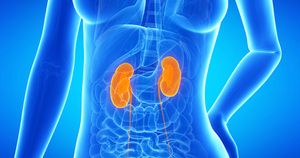

2. Co jest zaznaczone na grafice?

Obraz